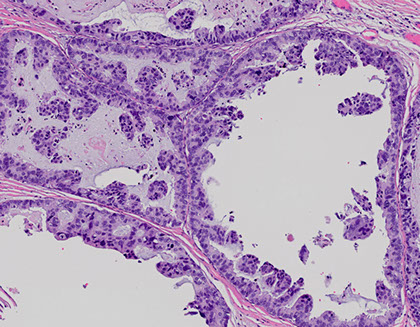

Tumor of the parotid c microcystic, papillary, and tubular patterns

- has a relation to acinic cell carcinoma and breast cancers, the genetics is mostly what makes it unique

- usually are slow growing lesions in the parotid of young males

- resembles secretory ca of the breast

IHC: (+) GCDFP-15, MUC1, BRST-2 and mammaglobin, CK, S100

- sometimes has (+) mucicarmine in intraluminal spaces

- negative HER2

Genetics: t(12;15)(p13;q25), ETV6-NTRK3 gene hybrid is diagnostic

MASC